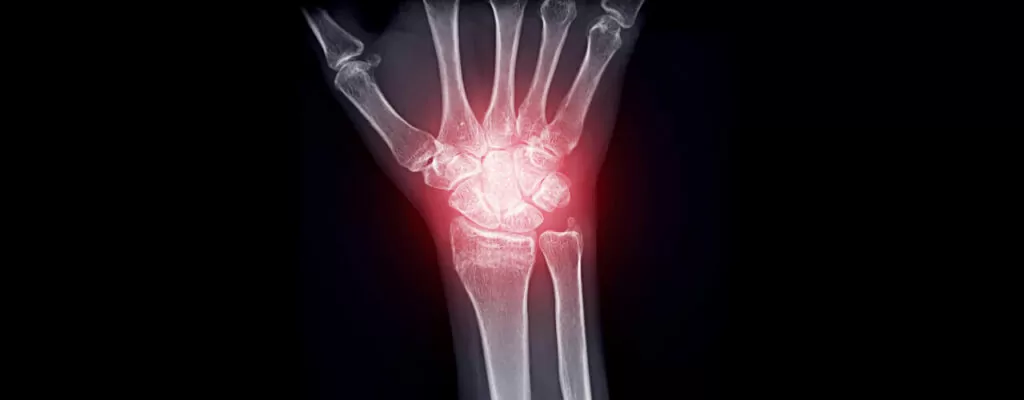

Recovering after surgery is more than just waiting for time to pass—it’s about taking the right steps to help your body heal. While the path to recovery after surgery is different for everyone, certain factors can slow progress, leaving patients feeling stuck or frustrated. That’s where expert guidance from can make all the difference. By